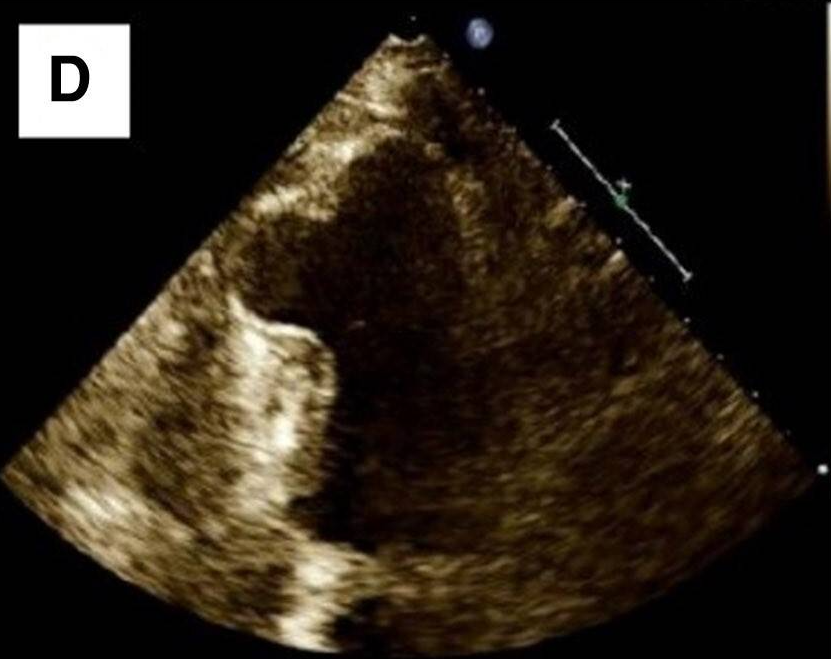

患者女性,69岁,因体检心电图发现T波改变,到心脏科就诊。患者既往无心脏相关病史及心血管危险因素。超声心动图检查发现室间隔肌部瘤样膨出,未发现左向右分流。冠状动脉造影证实冠状动脉正常。左心室造影可见室间隔肌部瘤形成。进一步行心脏CTA及MRI检查,结果显示巨大室间隔肌部瘤,直径与胸主动脉直径相当,未见血栓形成。鉴于患者无症状且无血流动力学影响,采取保守治疗策略,包括生活方式干预、定期心脏监测及规律随访。虽考虑预防性抗凝治疗可能会获益,但由于无血栓形成、血流动力学稳定且缺乏其他危险因素,最终未予实施。不抗凝虽可能增加血栓形成风险,但瘤体内的血流状态可能减少了血栓形成机会,避免了抗栓治疗相关的出血风险。嘱患者每6个月复查超声心动图,必要时行MRI检查。随访期间患者持续无症状且无新发异常,故继续维持原监测方案。

图为心电图、冠状动脉造影、经胸超声心动图、CTA及MRI检查结果。心电图显示v2-4导联T波改变(图A)。左心室造影可见室间隔肌部瘤(图C)。超声心动图显示室间隔瘤样结构(图D)。CTA与MRI均显示巨大室间隔肌部瘤(图E、F)。